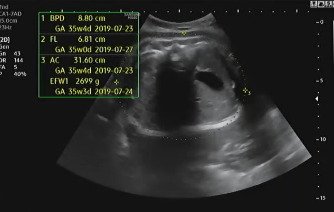

임신 37주가 되어 병원에 내원했다. 초음파를 보는데 아기는 건강하게 잘 있다고 열심히 태동을 하며 인사를 건네 왔다. 머리둘레(BPD), 허벅지 둘레(FL), 복부둘레(AC)를 측정하고 태아가 어느 정도로 성장하였는지 확인했다. 다행히 아기의 머리둘레가 주수보다 작게 나와서 자연 분만하기 좋을 것이라고 이야기를 했다.